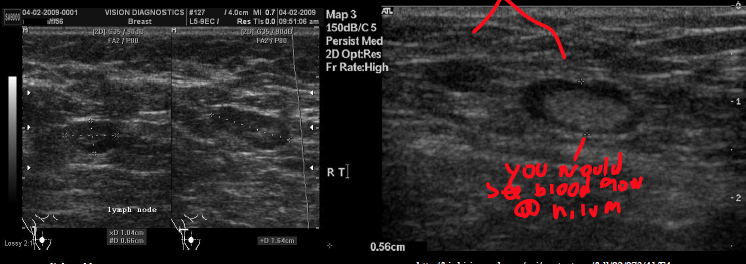

what is the normal size of a lymph nodE?

what is it’s sonographic appearance?

<1 cm

Homogeneous, ovoid, smooth borders, well defined

Hilum – echogenic due to fatty tissue

Hypoechoic

Nodes will not change shape or move like bowel will

what do you see int he top lt image?

mass effect

what are these examples of?

retroperitoneal lymph nodes